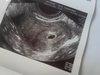

Przedstawiam wam moją małą krewetkę [emoji7][emoji23] Tak mówię na kropka.

Jestem już po pierwszym usg. Tak dla pewności, ponieważ jestem po poronieniu. Było w czerwcu. I wolałam dmuchać na zimne i dla świętego spokoju pokazać się lekarzowi. Dostałam luteine dopochwowo z racji poronień, lekarz się bał więc w razie czego mam brać. Kazał zrobić betę, jutro/czwartek zobaczyć jak przyrasta i sprawdzić progesteron. Mam brać euthyrox dalej. Ale wynik testosteronu skoczył. Z 1,03 do 2,61. Wyniki tarczycy podobno są dobre ale czekam na swoją zaufaną lekarkę. Jeszcze dziś zadzwonię do niej. Wykupiłam kwas foliowy. Ale nie pamiętam ile mam go brać. Nie brałam wcześniej. Owulacja była z prawego jajnika. Trochę mnie to martwi. Bo cały czas z prawego coś się dzieje. No i na razie jest w porządku. Zobaczymy jak beta. Chciałabym odetchnąć z ulgą ale nie umiem tak się boję [emoji17] O dzidzie. Modlę się, żeby było dobrze wszystko.

Jestem już po pierwszym usg. Tak dla pewności, ponieważ jestem po poronieniu. Było w czerwcu. I wolałam dmuchać na zimne i dla świętego spokoju pokazać się lekarzowi. Dostałam luteine dopochwowo z racji poronień, lekarz się bał więc w razie czego mam brać. Kazał zrobić betę, jutro/czwartek zobaczyć jak przyrasta i sprawdzić progesteron. Mam brać euthyrox dalej. Ale wynik testosteronu skoczył. Z 1,03 do 2,61. Wyniki tarczycy podobno są dobre ale czekam na swoją zaufaną lekarkę. Jeszcze dziś zadzwonię do niej. Wykupiłam kwas foliowy. Ale nie pamiętam ile mam go brać. Nie brałam wcześniej. Owulacja była z prawego jajnika. Trochę mnie to martwi. Bo cały czas z prawego coś się dzieje. No i na razie jest w porządku. Zobaczymy jak beta. Chciałabym odetchnąć z ulgą ale nie umiem tak się boję [emoji17] O dzidzie. Modlę się, żeby było dobrze wszystko. Zobacz załącznik 890182